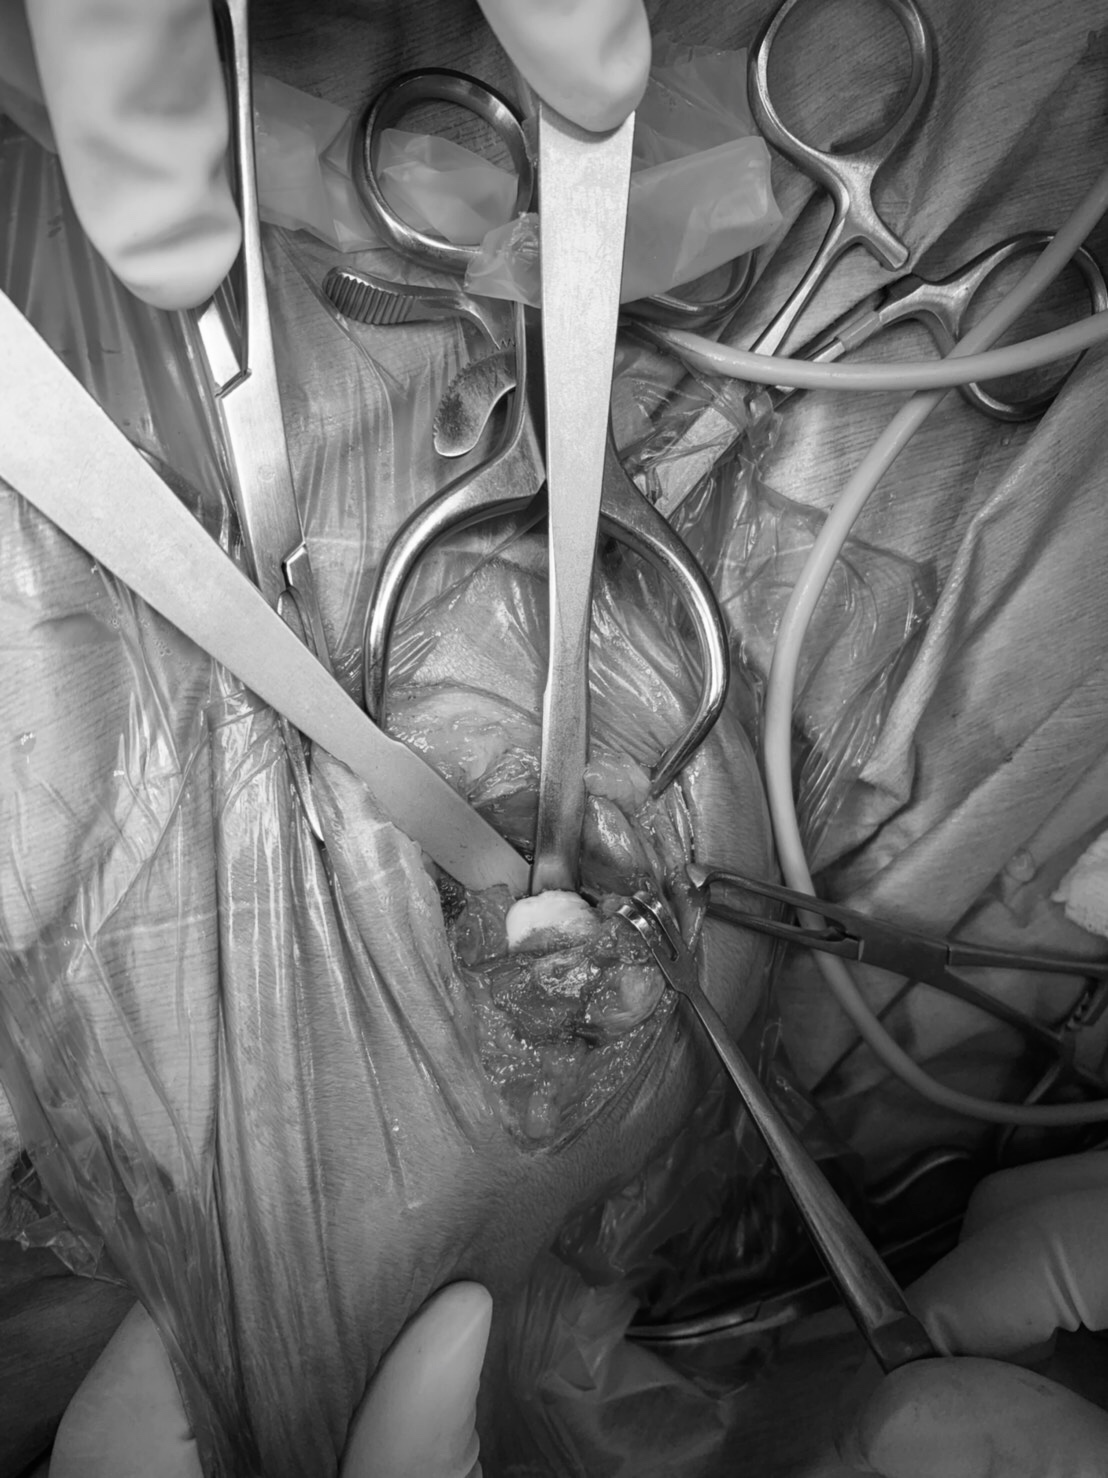

術中、骨頭・骨頚部切除前

切除後の骨頭部。本来は滑らかな球形ですが、表面がボロボロになり剥離してしまっているのが分かります